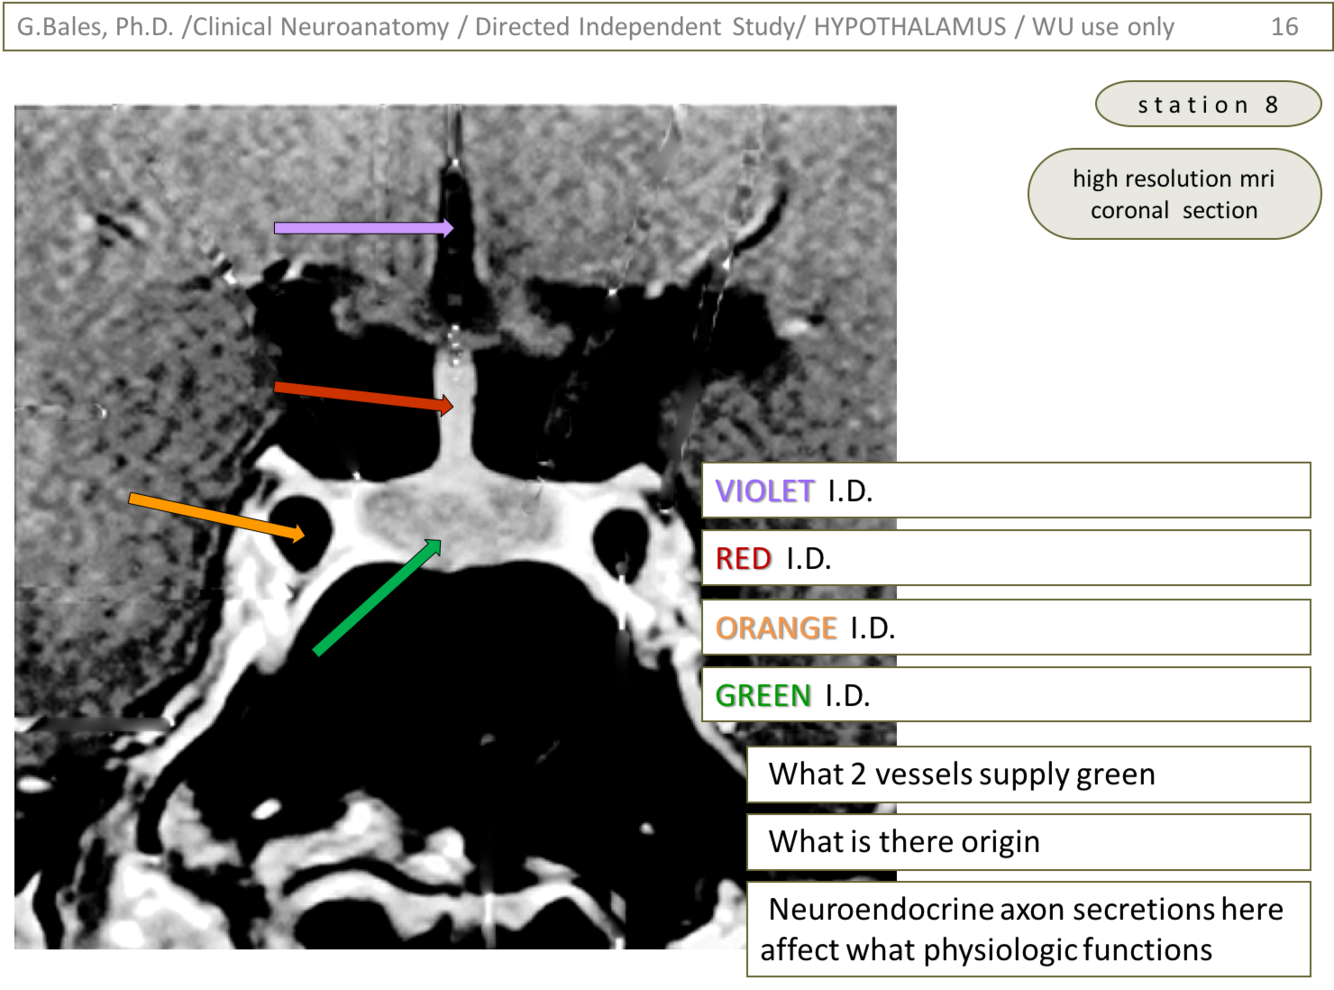

1) Violet – 3rd ventricle

2) Red – pituitary stalk

3) Orange – internal carotid a.

4) Green – pituitary

1) 2 vessels supply green: inferior and superior hypopheal a.

2) Origin of these 2 vessels is the internal carotid a.

3) Secretion effects what physio. functions: regulation of other glands; pituitary is ‘master gland’